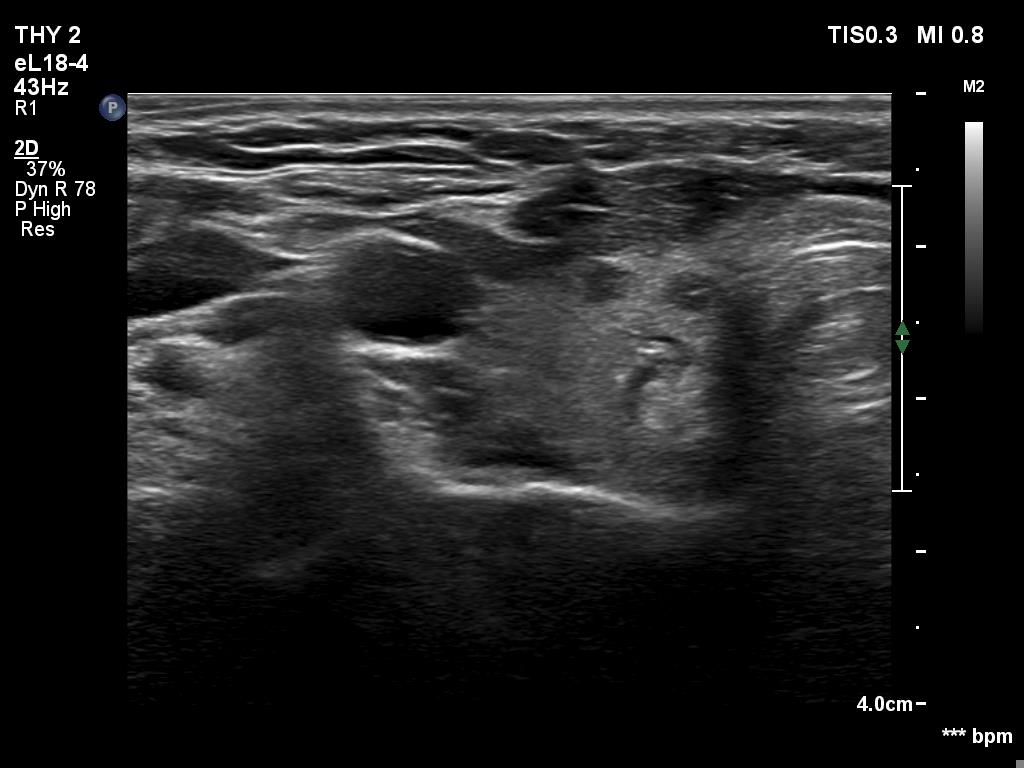

Second examination 6 month later (2nd row of images)

Clinical presentation. The patient was referred for evaluation of hyperparathyroidism. Elevated calcium and parathyroid hormone levels were found during the first evaluation. (These findings were not yet available when I first examined the patient.) Further evaluation disclosed a hyperfunctioning right lower parathyroid. The patient was operated on but no parathyroid tissue was found on histopathology. (A more experienced parathyroid surgeon was quarantined at the scheduled time of the operation, so a less experienced colleague performed the surgery.) Both hypercalcemia and hyperparathyroidism have persisted.

Ultrasonography revealed a hypoechoic mass corresponding to the right lower parathyroid.

Cytology resulted in benign lesion, a pattern which corresponded to a parathyroid adenoma.

The patient was reoperated and histopathology disclosed a parathyroid adenoma according to the right lower parathyroid.

If we compare the first and second ultrasound examination, it is evident that the ultrasound examination was not performed according to the rules of the profession at the first visit. (I will just mention that although in this case we only videotaped part of the entire study, we obviously overlooked the parathyroid gland under the right lobe. The reason for this is that we did not examine the part below the thyroid in the transverse section, and in the longitudinal section we started to examine the lower part of the thyroid too medially.)

Parathyroid surgery requires a lot of practice. The less experienced colleague who undertook the surgery judged that he would find a 1.5-centimeter lesion. But he also failed.